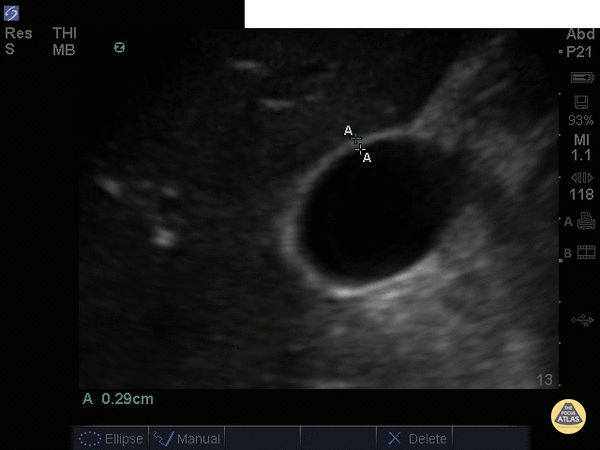

Biliary - Gallbladder Wall Measurement

This normal gallbladder image shows how to measure the anterior wall of the gallbladder. A normal gallbladder wall should be less than 3mm. The posterior wall should not be measured as it can appear enlarged due to artifact. Justin Bowra MBBS, FACEM, CCPU Emergency Physician, RNSH et al.